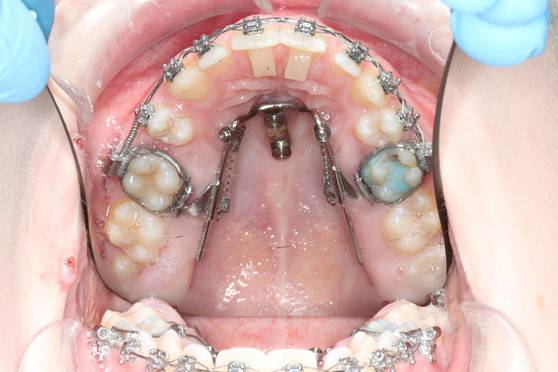

De indsættes i knoglen under lokalbedøvelse.

De kan sidde enten i den ene side eller i ganen.

Ved hjælp af skruerne kan man flytte enten en eller flere tænder uden at resten af tænderne belastes.